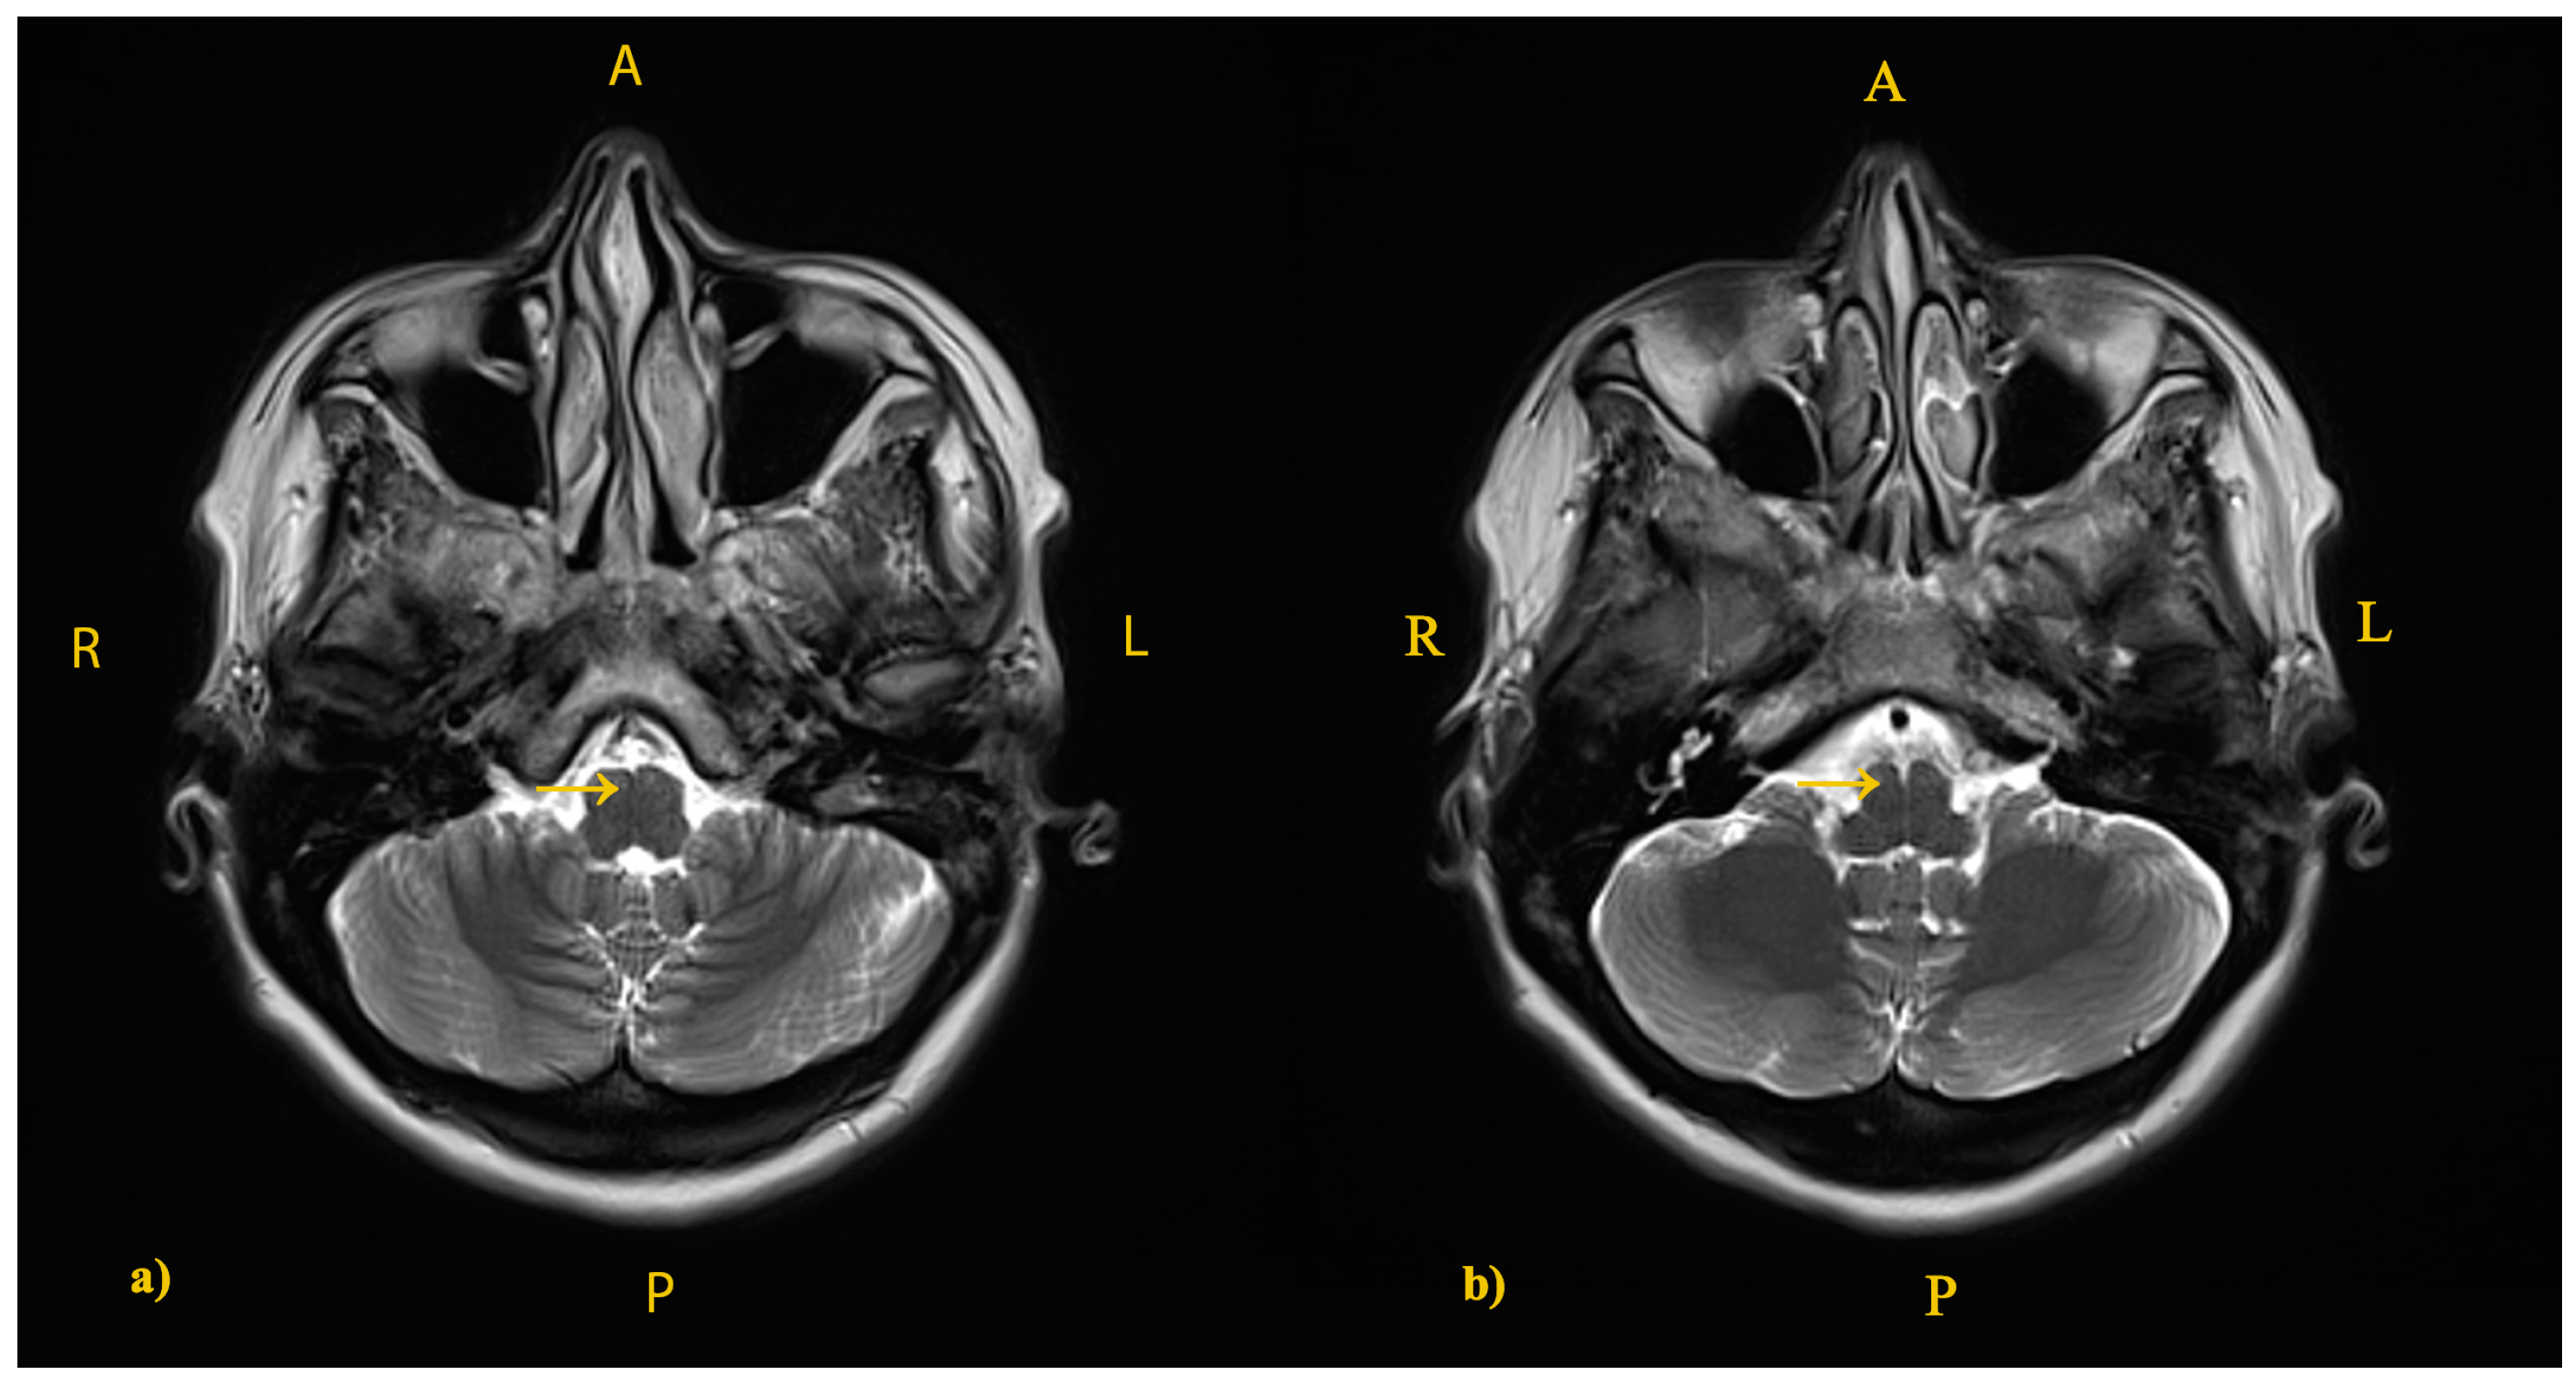

2. The Case: An Intriguing Case Unraveling Clinical and Paraclinical Complexities